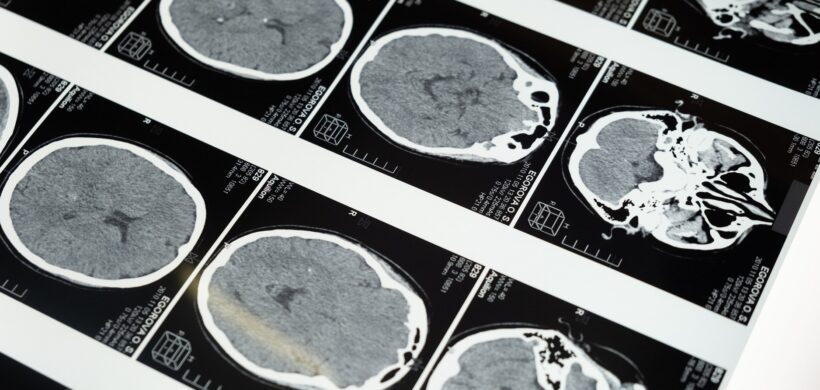

Impacto del tratamiento con NeuroEPO en la evaluación neuropsicológica de pacientes con alzhéimer

Urrutia Amable a, S. Sosa Pérez a, D. López Brito a, A I. Peñalver Guía b, G. Bringas Sánchez b, L. Pérez Ruiz c, T. Rodríguez Obaya c, Carmen M. Valenzuela Silva c y A. Fernández Nin d | a Hospital General Docente Iván Portuondo, San Antonio de los Baños, Artemisa, Cuba. b Instituto de Neurología y Neurocirugía (INN), La Habana, Cuba. c Centro de Inmunología Molecular (CIM), Playa, La Habana, Cuba. d Centro de Neurociencias de Cuba (CNEURO), La Habana, Cuba. La enfermedad de Alzheimer (EA) es considerada actualmente la forma más común de demencia en los adultos mayores, representando alrededor del 60 al 70% de los casos. El enfoque terapéutico o farmacológico de la EA actualmente es sintomático y no curativo. Disímiles ensayos clínicos con diversos productos para el tratamiento de la EA han fracaso, otros aún continúan en la búsqueda de eficacia, seguridad o una posible cura. Desde finales del siglo pasado en nuestro país se produce la eritropoyetina humana recombinante (EPOhr), con diversos resultados científicos que han demostrado su acción hematopoyética, neuroprotectora, antioxidante, anti-inflamatoria, neurotrófica y angiogenética. Debido a ello se decidió desarrollar una eritropoyetina con bajo contenido de ácido siálico no hematopoyética (NeuroEPO); ampliamente estudiada con iguales acciones neuroprotectoras que su antecesora. El presente estudio tiene como objetivos principales evaluar la eficacia del tratamiento con NeuroEPO en pacientes cubanos con síndrome demencial tipo Alzheimer leve/moderado, en términos de la reducción en la progresión del deterioro cognitivo; así como determinar su efecto en las manifestaciones psicoconductuales. Participaron 174 pacientes con diagnóstico de síndrome demencial tipo Alzheimer leve/moderado como parte de un ensayo clínico, aleatorizados en 3 grupos con 58 pacientes cada uno: A y B recibieron dosis de 0,5 mg y 1 mg respectivamente; y C recibió placebo. Se demostró la eficacia del tratamiento con NeuroEPO, con diferencias en el puntaje del ADAScog11 al finalizar el estudio de 8 y 9 puntos en los grupos tratados con relación al grupo placebo (p=0.000, IC 95%) en la población por protocolo, mejorando también el porcentaje de cambio del CIBIC Plus (p=0.000, IC 95%), con resultados significativos en el resto de las pruebas neuropsicológicas realizadas. Además, éstos lograron una disminución de la sintomatología psicoconductual (p=0.000, IC 95%) respecto al grupo control. Como conclusiones fundamentales se evidenció una reducción en la progresión del deterioro cognitivo en los grupos que recibieron NeuroEPO con relación al grupo placebo, reflejada en la mejoría cognitiva y psicoconductual al finalizar el estudio. Acceso al artículo completo.